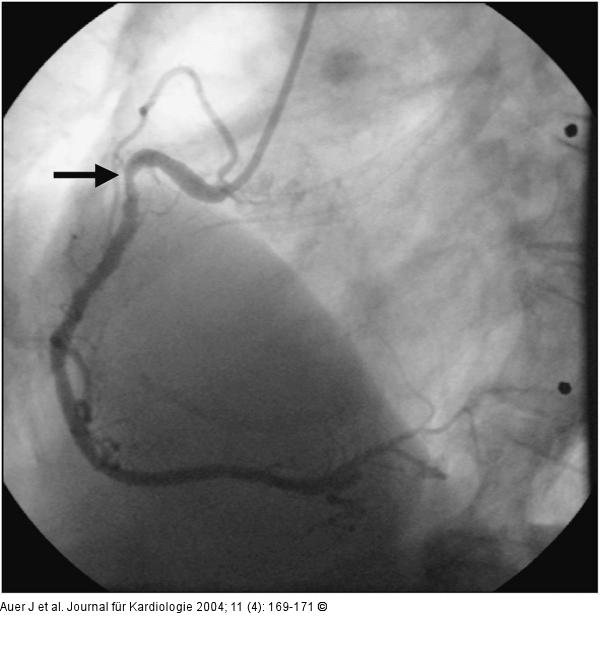

Abbildung 4: Akutes Koronarsyndrom - Stenose der linken Herzkranzarterie 50%ige Stenosierung in der RCA proximal |

Abbildung 4: Akutes Koronarsyndrom - Stenose der linken Herzkranzarterie

50%ige Stenosierung in der RCA proximal |